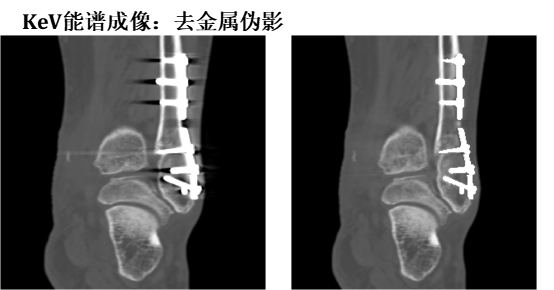

三、能谱单能成像